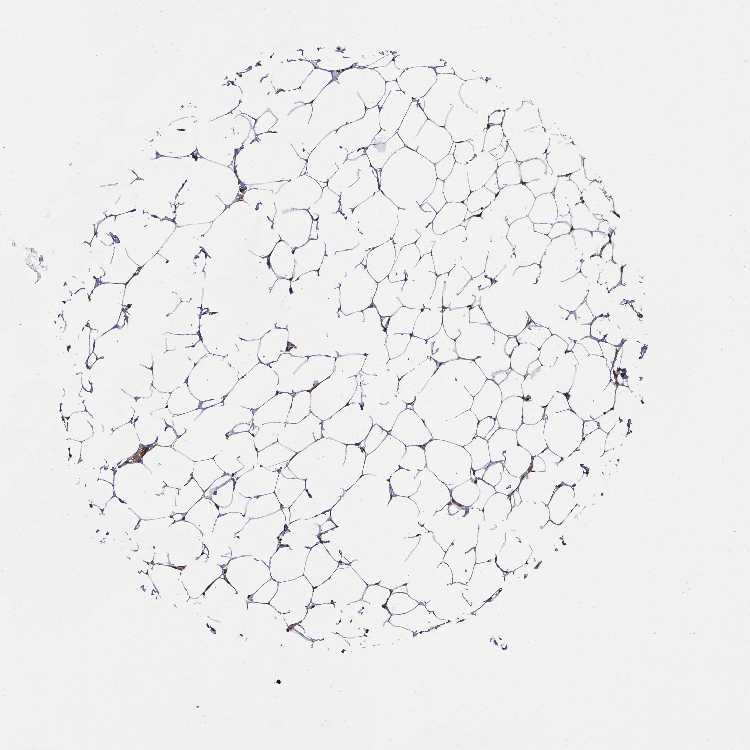

BREAST - Antibody stainingi

Antibody staining in the annotated cell types in the current human tissue is reported as not detected, low, medium, or high, based on conventional immunohistochemistry profiling in selected tissues. This score is based on the combination of the staining intensity and fraction of stained cells.

Each image is clickable and will lead to virtual microscopy that enables deeper exploration of all samples and also displays staining intensity scores, fraction scores and subcellular localization as well as patient and tissue information for each sample.

Antibody HPA045821Antibody HPA054352Antibody CAB012229

Adipocytes Not detectedLowMedium